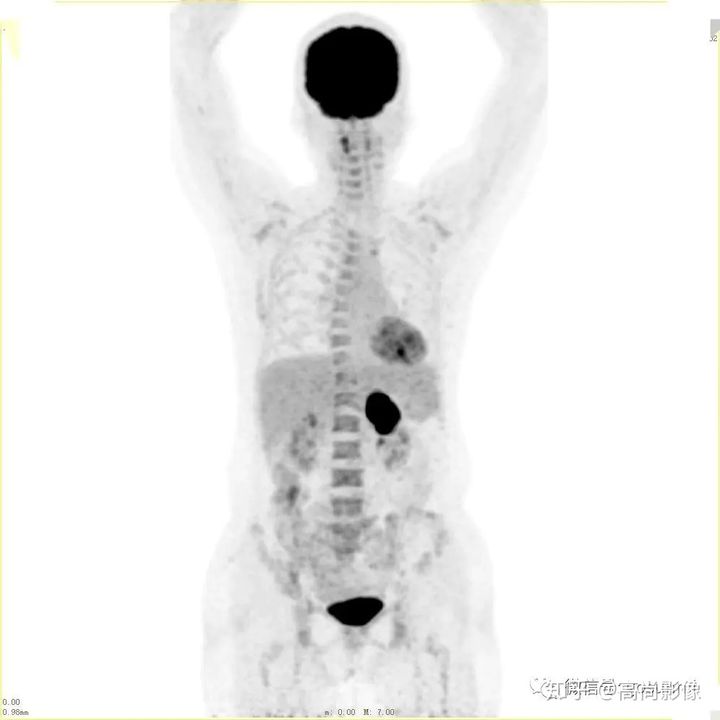

(右肺癌全身多發(fā)轉(zhuǎn)移)

(右肺上葉中央型肺癌)

方大爺?shù)腜ET/CT結(jié)果強(qiáng)烈提示肺癌伴全身多發(fā)轉(zhuǎn)移,已經(jīng)失去手術(shù)機(jī)會,但仍有繼續(xù)化療的機(jī)會。